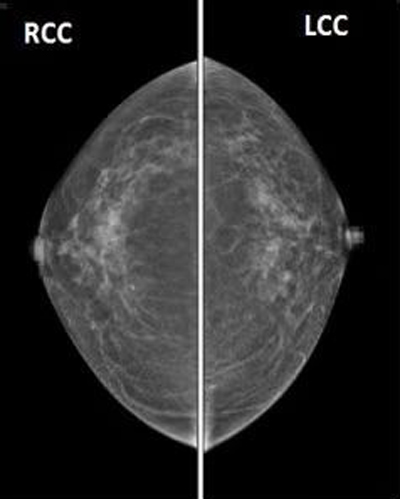

经调试已正式投入临床使用,该设备作为新一代数字化二维乳腺机,配备了双焦点高速X射线管组件,非晶硅高分辨率平板探测器,低剂量钨靶球管降低辐射剂量。可以提供高质量的检查图像,并且可根据需要调整图像的对比度和亮度,有助于致密乳腺高清成像,提升早期病灶检出率 ,高效助力乳腺疾病早筛早诊;依托智能压迫系统自动调整压迫力,保证受检者舒适体验,用心关爱乳腺健康,成就致密乳腺优质成像。

乳腺钼靶,全称乳腺钼靶X线摄影检查,是一种低剂量乳腺X线拍摄乳房的技术,是目前诊断乳腺疾病的首选和最简便、最可靠的无创性检测手段。留取的图像可供前后对比,不受年龄、体形的限制,目前已作为常规的检查。它能清晰显示乳腺各层组织,可以发现乳腺增生、包块、钙化及各种乳腺良恶性肿瘤,可观察到小于0.1毫米的微小钙化点及钙化簇,是早期发现、诊断乳腺癌的最有效和可靠的检查方法。